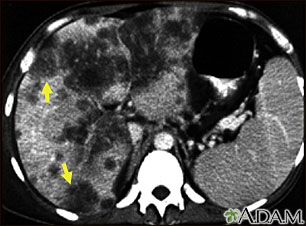

A CT scan of the upper abdomen showing a widespread (disseminated) carcinoma of the liver (hepato cellular carcinoma). The liver is the large organ on the left side of the picture. Note the moth-eaten appearance.